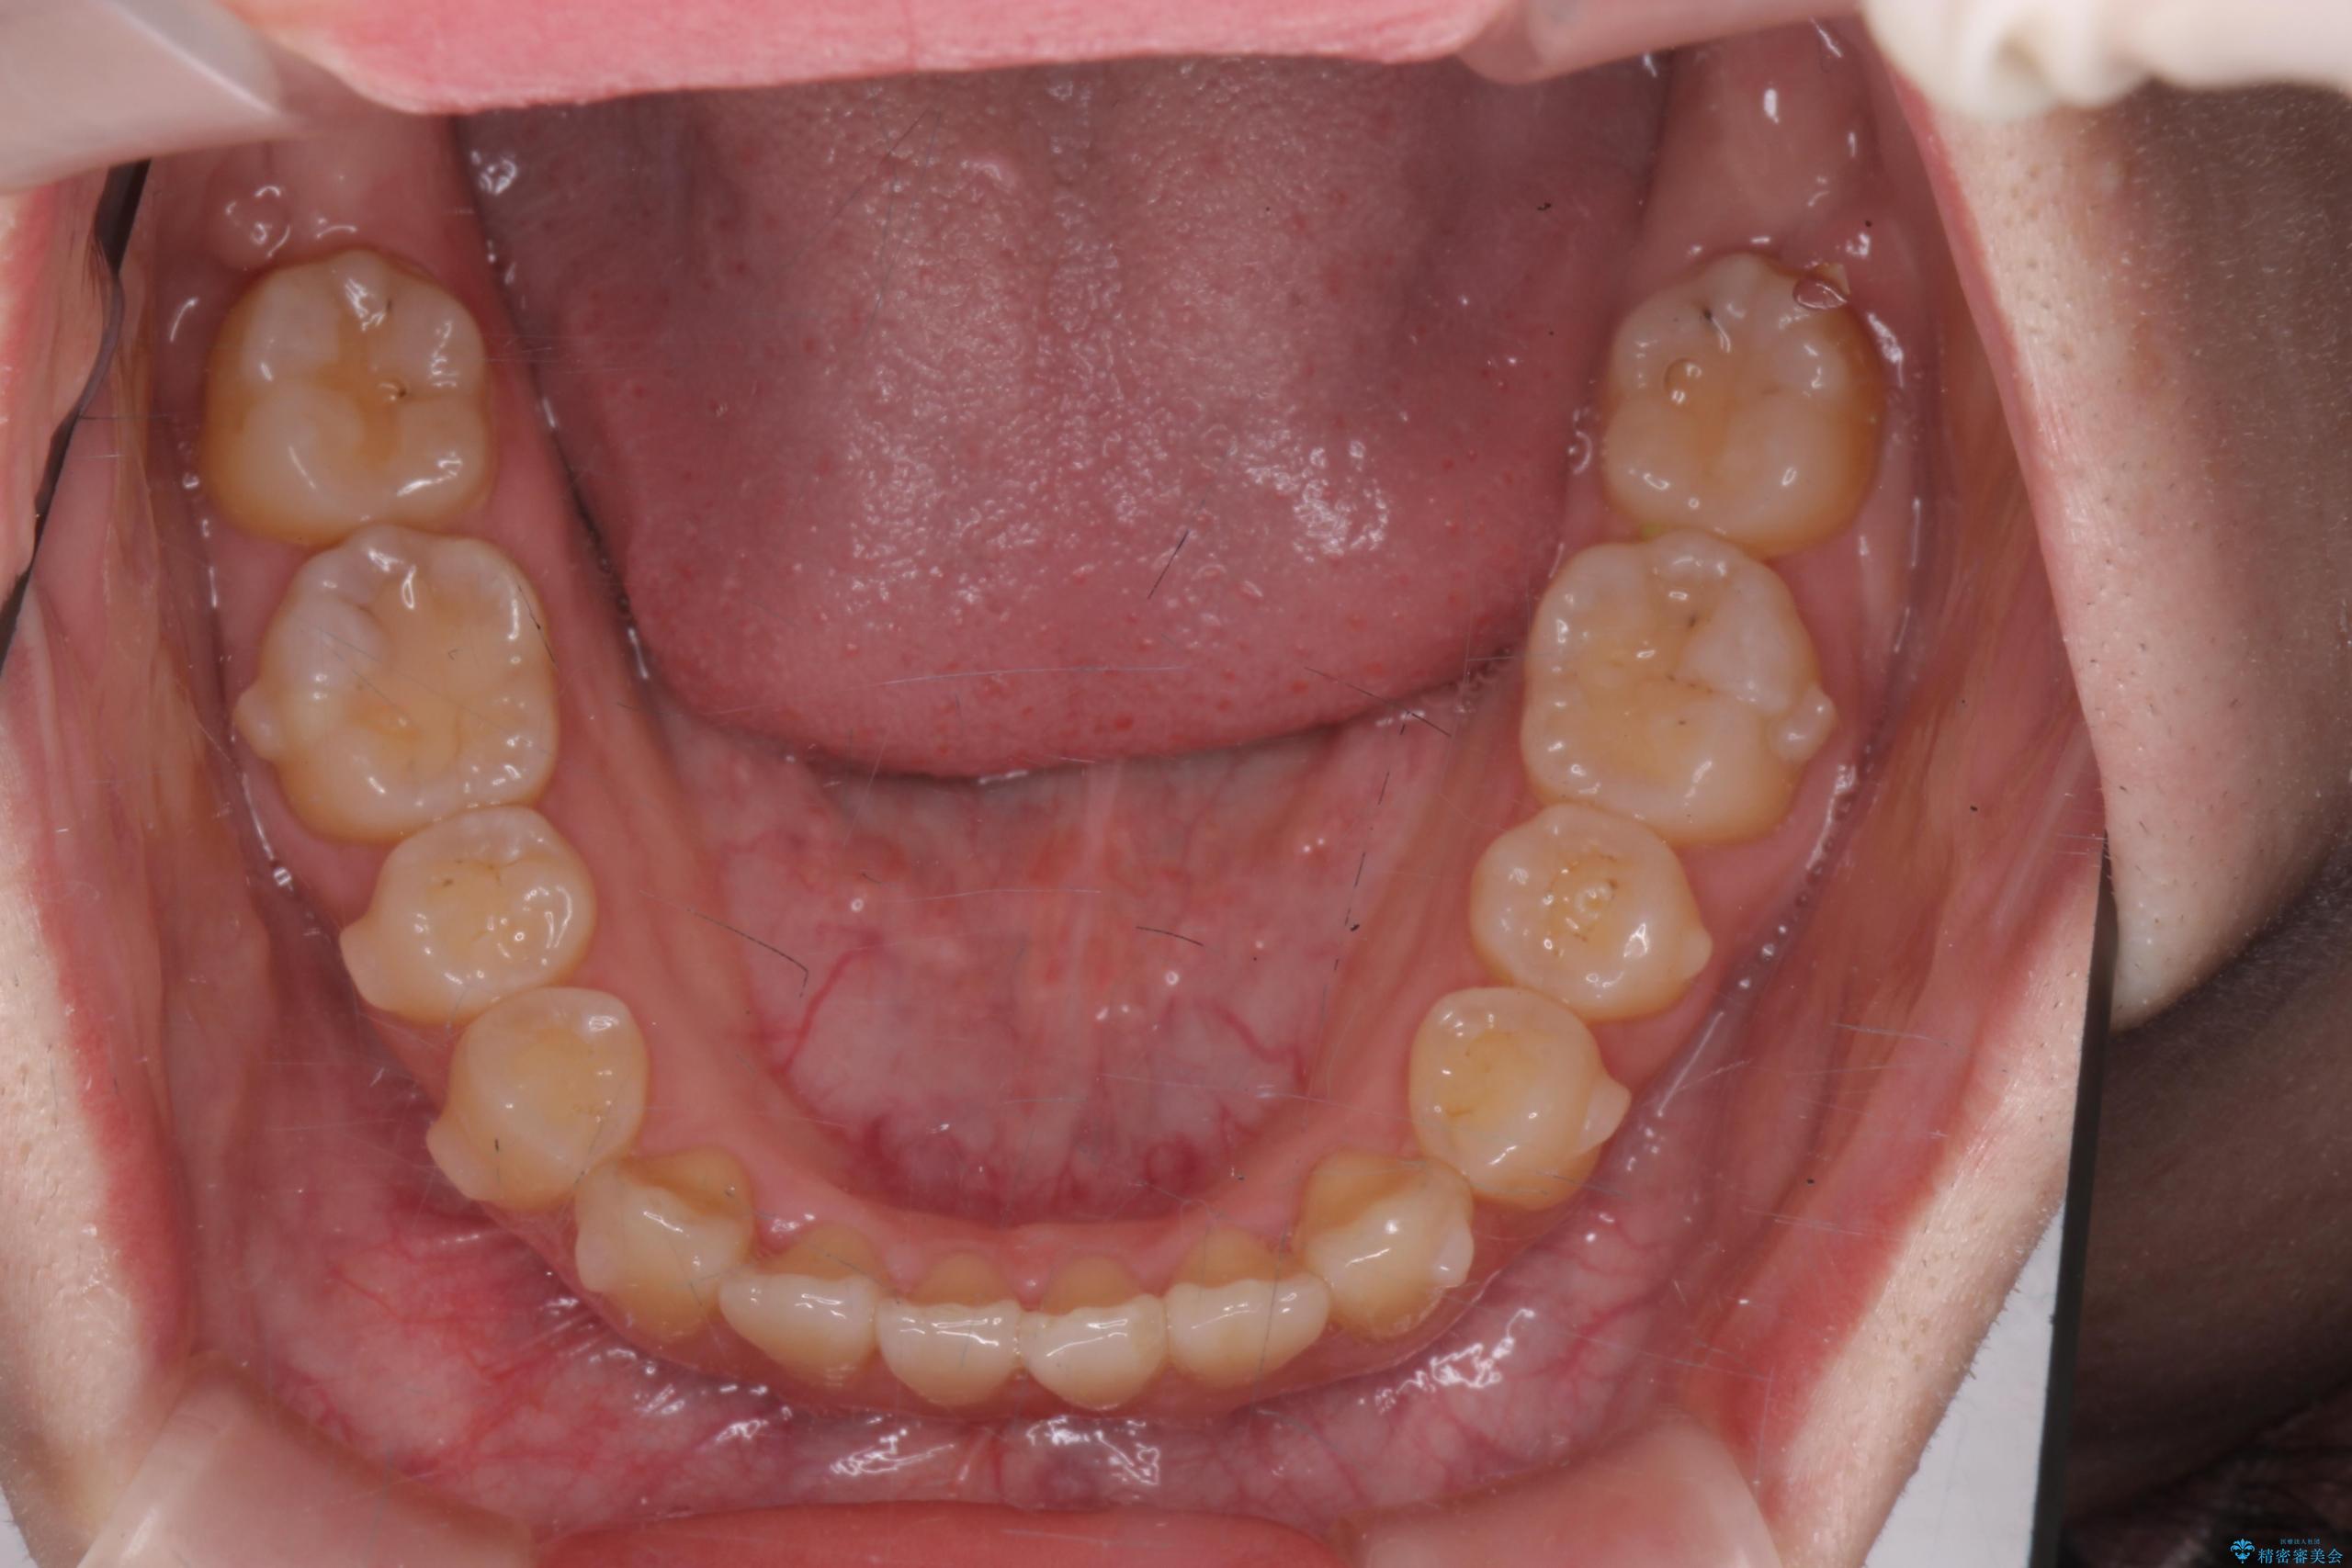

前歯のねじれが気になる、歯並びを改善したいとご来院された患者様です。

歯のねじれをきれいに取るのは、インビザライン(マウスピース矯正)だけでは難しい動きです。そのため、事前に4か月間の部分ワイヤー矯正を行い、治療期間を短くし、より美しい仕上がりを目指す計画です。

前歯が綺麗に並び、大変ご満足いただけました。